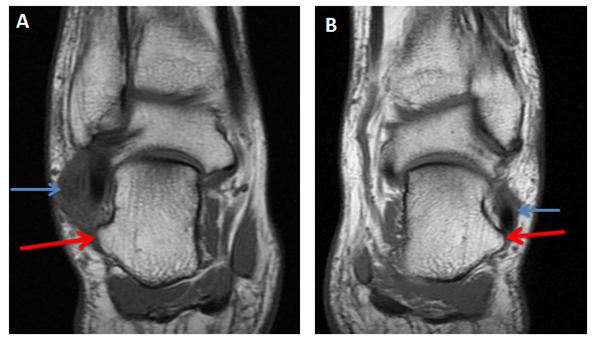

Coronal fat saturated proton density MRI image of the right ankle showed both peroneal tendons located above the peroneal tubercle, they were surrounded with soft tissue swelling and high T2 signal intensity which indicates fluid effusion. Abnormal signal intensity was also seen within both peroneal tendons indicating tendonitis. The left ankle showed a prominent peroneal tubercle. Peroneal tendons were normal and intact (Figure 4).

Figure 4 (A) Coronal fat saturated proton density MRI image of the right ankle shows the hypertrophic peroneal tubercle (red arrow). Both peroneal tendons are located above the tubercle, they are surrounded with soft tissue swelling and high T2 signal intensity (blue short arrow). Abnormal signal intensity is also seen within both peroneal tendons. (B) Left ankle for comparison shows a prominent peroneal tubercle but normal peroneal tendons.